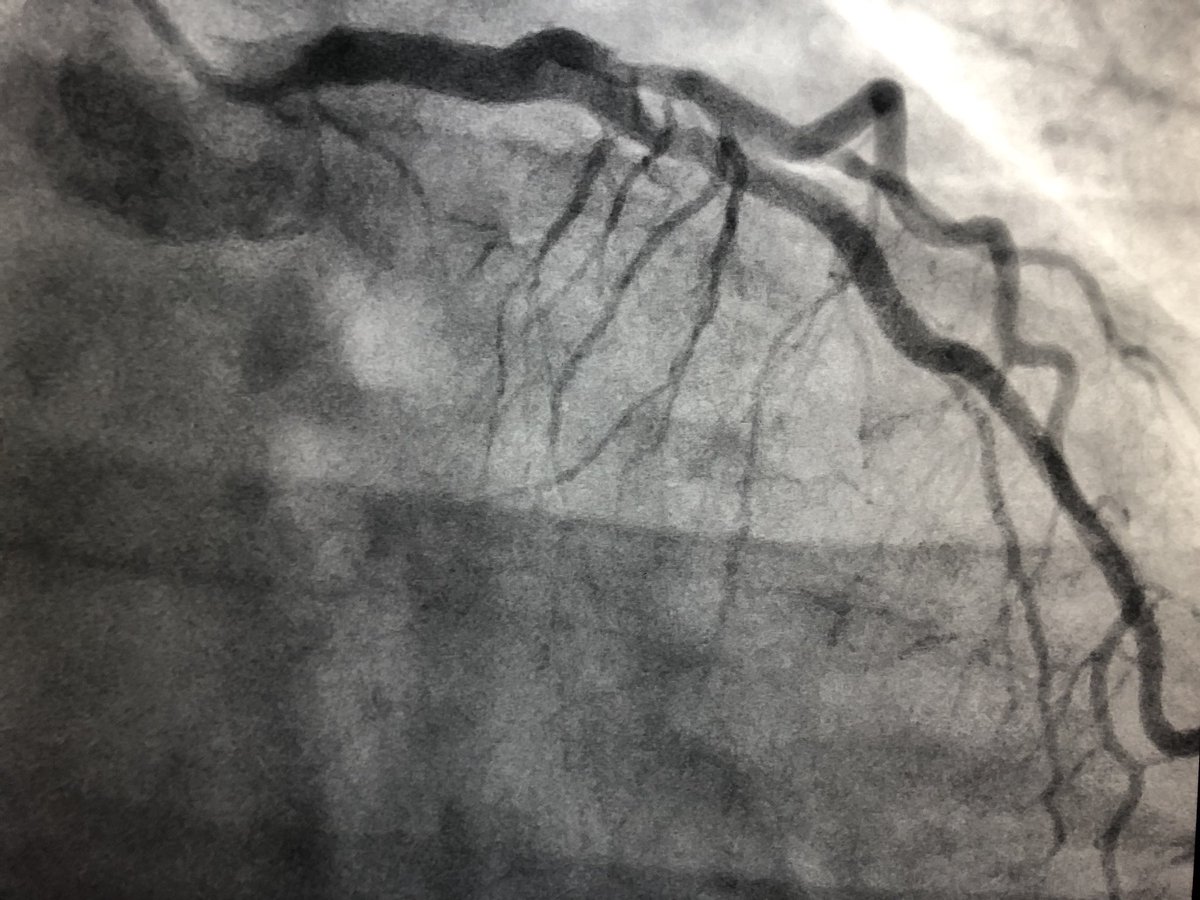

Hypothetical pt - mid 60’s w angina - multi-vessel dz including 🔹RCA CTO J -CTO score 2 🔹 All non-CTO lesions fixed (angina resolves) 🔹EF 60% 🔹high volume CTO center ❓What to do for RCA CTO @TAVRBot @RadialFirstBot @mmamas1973 @jtsaxon @djc795 @JAG24851 @DrBillLombardi